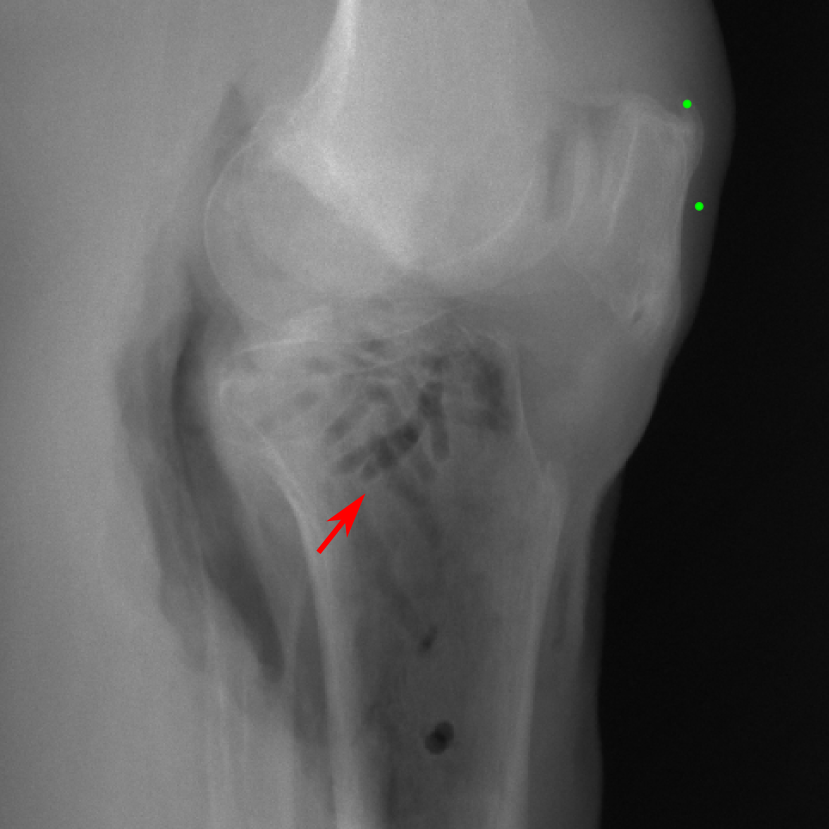

5.4 Real Knee Data with Metal Implants

Refer to caption

Figure 13: Three examples of synthetic perspective projection images for training, intensity window: [0, 4]. The appearance (e.g., image contrast and metal image resolution) of such DRR training images is different from that of real projection images in Fig. 14.

0superscript00^{\circ} perspective

(a) 32.56, 109.85

(b) 18.91, 19.54

(c) 28.11, 112.16

(d) 15.80, 19.27

0superscript00^{\circ} and 180superscript180180^{\circ} RGB

DRR reference

(e) 29.72, 111.80

(f) 17.14, 19.38

Pix2pixGAN

(g) 29.72, 111.80

(h) 17.50, 19.70

TransU-Net

(i) 29.72, 111.80

(j) 16.23, 19.25

Figure 14: The results for the real cadaver leg data. The green dots mark the positions of landmarks in the corresponding reference images. In the first column, the arrows indicate the bone cavity/fracture structures. In the second column, the solid lines mark the widths and heights of the metals. The green ones are measured from the DRR reference, while the red ones are measured in the corresponding perspective projection image. In the last column, the lines mark the centerlines of the metal screws, where the green lines are those from the reference image. The lengths of the lines in mm are displayed in their corresponding subcaptions. Intensity window: [0, 4]. Please zoom in for better visualization.

The complementary view setting for learning perspective deformation is also evaluated on real CBCT projection data. In this evaluation, real CBCT projection data from a dataset of knees with metal implants is used for testing, while DRRs created from volumetric CT datasets with inserted metals is used for training. Three exemplary DRR perspective projection images for training are displayed in Fig. 13, in which synthetic metal implants are inserted [34]. The appearance, e.g., image contrast and metal image resolution, of such DRR training images is different from that of real projection images in Fig. 14. In Fig. 14, the results for three knees, with and without metal implants, are displayed. The first and second rows are the 0superscript00^{\circ} and 180superscript180180^{\circ} perspective projections, respectively, rebinned to the virtual detector with geometric calibration based on their respective principal points and projections of the world origin. The third row displays their difference images, where the magnitude of deviation increases from the center towards the outside like it does in DRRs with an ideal scan trajectory (e.g., Fig. 6(e)), although real projection data suffer from various physical effects like beam hardening and Poisson noise. The fourth row displays the RGB stacks of 0superscript00^{\circ} and 180superscript180180^{\circ} perspective projection images. The magenta and green regions indicate structures with considerable perspective deformation, for example, the knee patella in Fig. 5.4, the top parts of the two metals in Fig. 5.4, and the bottom two screws in Fig. 5.4. The fifth row displays reference images, which are orthogonal projections of iterative reconstruction volumes from measured CBCT projection data. In the reference images, a total of five landmarks are selected, with the positions being marked by the green dots: In Fig. 5.4, two positions at the edges of the knee patella are marked; In Fig. 14(e) and Fig. 14(f), one position at the left edge of the fibula is marked for each image. In addition, a rectangular frame for the two metals is marked by the green dashed lines, while its width and height are indicated by the green solid lines, which are 29.71 mm and 111.99 mm, respectively. In Fig. 14(f), the centerlines of the bottom two screws are sketched by the green lines, which have the lengths of 17.14 mm (middle screw) and 19.38 mm (bottom screw). The corresponding rectangular frame for the two metals and the screw centerlines in the perspective projection images are marked as well, but in red color. In Fig. 14(a), the width and height of the metals are 32.56 mm and 109.85 mm, which have deviations of 2.84 mm and -1.95 mm to the reference ones, respectively. In Fig. 14(b), the centerline lengths are 18.91 mm and 19.54 mm, which have deviations of 1.77 mm and 0.16 mm, respectively. Although the bottom screw has little length deviation to the reference, the orientations of both screws are obviously deviated. The sixth row shows the results of Pix2pixGAN using 0superscript00^{\circ} and 180superscript180180^{\circ} polar inputs. For all of the landmarks, the green reference dots are all located accurately in the Pix2pixGAN images. The rectangular reference frame also accurately covers the metals in Fig. 14(g). In Fig. 14(h), although the two red centerlines do not exactly overlap with the green one, they are very close in lengths and orientations. Please zoom in for better visualization.

The region-of-interest covering the cavity/fracture structures indicated by the red arrow in Fig. 14 has been enlarged in Fig. 15 for better visualization of image resolution. In the real 0superscript00^{\circ} perspective projection ROI (Fig. 15(a)), the cavities and bone edges appear sharp. The presence of Poisson noise can also be visualized to some degree. In the DRR reference ROI (Fig. 15(b)), the cavities and bone edges appear blurry. This is likely caused by the partial volume effect in the intermediate 3D reconstruction volumes. In the Pix2pixGAN output (Fig. 15(c)), there is a slight smoothing effect. For example, the fine edge indicated by the arrow is blurred and the Poisson noise is reduced. But in general, image resolution is preserved for most anatomical structures, e.g., the cavities.